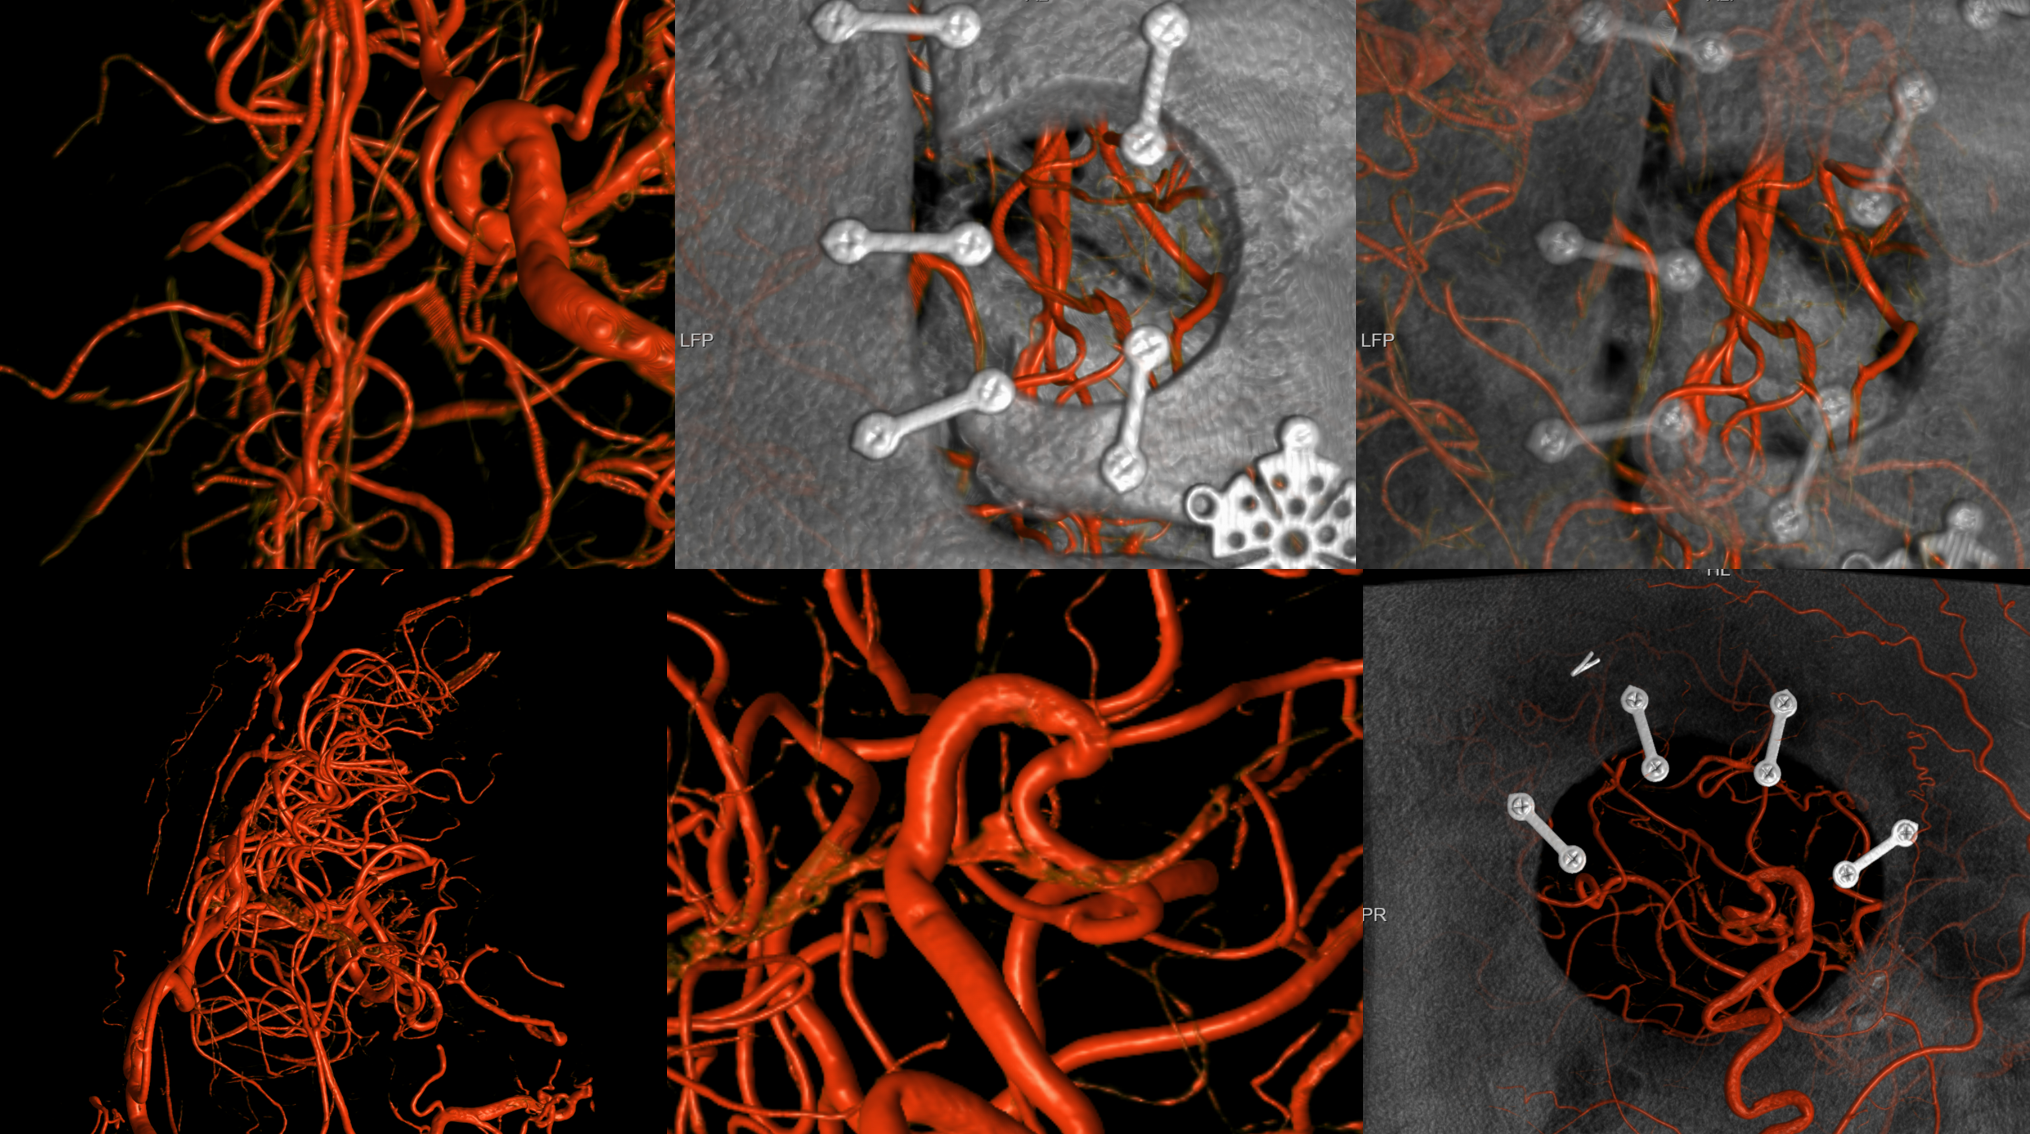

Bilateral CBCT Injections. A big bonus — the ACA-ACA bypass now seems to be patent! Cant see that from 2D images really at this stage. We did not realise this at first but became clear later

A3-A3 bypass more images

Robust bypass supports superior division and some more

Bypasses. Note A3-A3 patent bypass, as well as STA-MCA. Both seen thru radiolucent skull windows